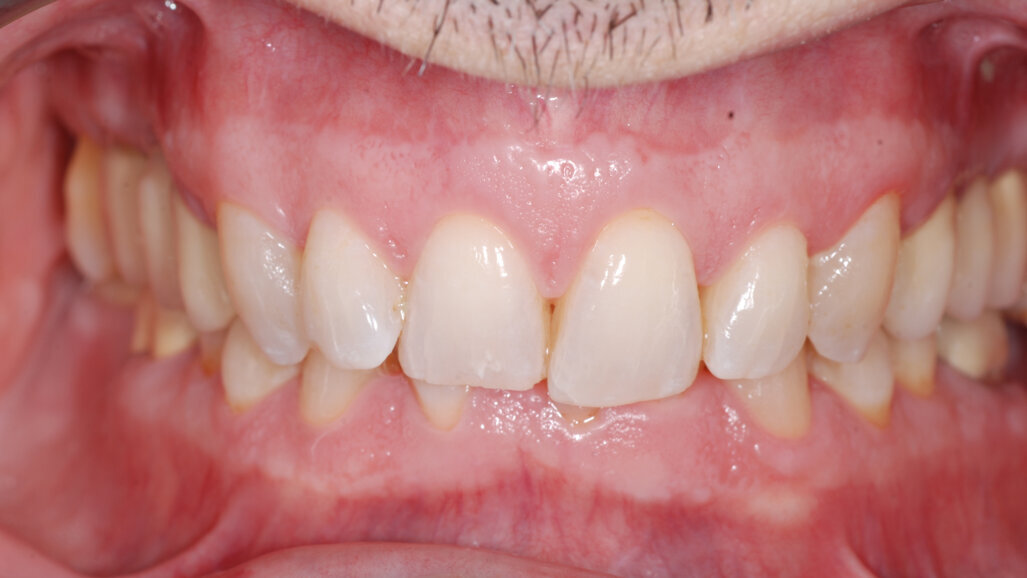

A 37-year-old male patient presented with the chief need for re establishing anterior alignment in both arches. Facial analysis showed a short face with a flat profile but proper chin projection (Figs. 9–12), and clinical examination revealed a skeletal Class I (ANB = 0.89°) and dental Class I malocclusion with severe deep bite (almost 100%), a deep curve of Spee, normal maxillary central incisor torque (Ui–FH = 110°), mild maxillary crowding and moderate mandibular crowding (Figs. 13–18). The deep bite components were represented in this patient by the severe skeletal condition of hypo divergent pattern (FMA = 14.24°) with normal maxillary and mandibular incisor inclination and decreased gonial angle (110.46°). Analysis of the cephalometric radiograph indicated a reduced lower anterior facial height, combined with a hypo-divergent pattern (Fig. 19). The only treatment option suggested was orthodontic treatment with aligners for deep bite correction with all the features described (bite ramps, pressure area, 3D curve of Spee levelling, Class II elastics and heavy occlusal contacts).

At the end of the treatment, Class I canine and molar relationships were obtained, maxillary incisor inclination was slightly increased (Ui–FH = 112°), mandibular incisor inclination (IMPA = 97.09°) was fully corrected by means of proclination and the divergency was slightly increased (SN–GoGn = 27°) because of the relative posterior extrusion and use of Class II elastics—a small variation (1°), which is interesting considering the age of the patient (Figs. 25–35). A balanced smile arc was obtained with an ideal relationship between the maxillary incisors and lower lip, and torque control of the lateral and posterior segments generated a broader smile.

At the one-year follow-up in retention (Vivera retainers with bite ramps, Align Technology), the result was stable and intercuspation was improved (Figs. 38–42).